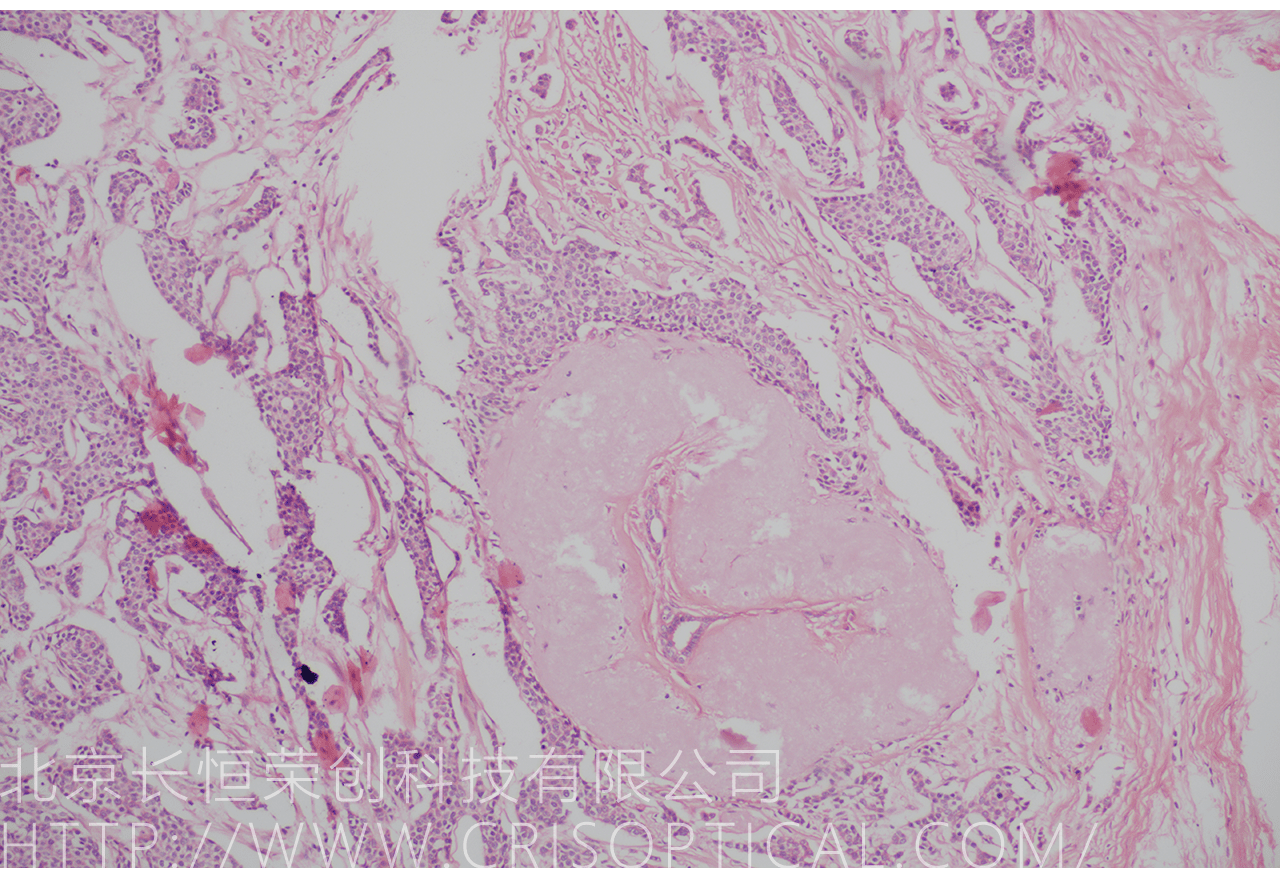

腫瘤診斷:對癌癥和其他腫瘤的病理切片觀察是確定腫瘤類型、分級和分期的關鍵步驟。醫(yī)生通過觀察組織樣本中的細胞形態(tài)、核形狀、分裂活性和其他特征,可以識別腫瘤的類型,幫助決定治療方法。